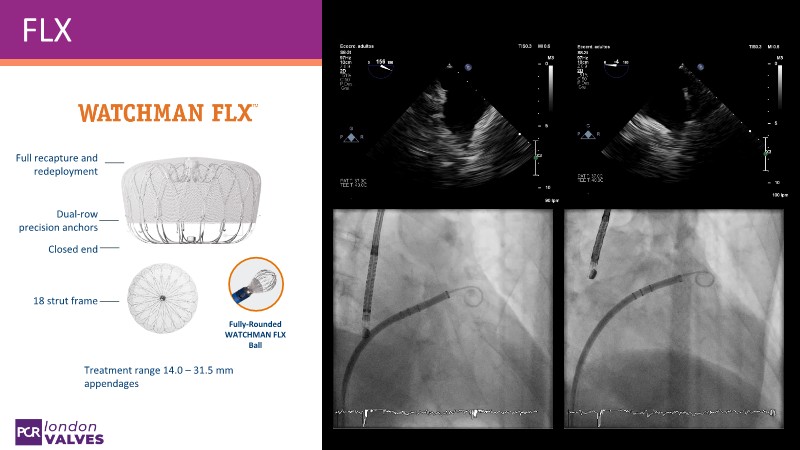

Explore the forefront of left atrial appendage (LAA) closure with this session focusing on the latest innovations and clinical opportunities. Topics include recent data on WATCHMAN FLX PRO and VersaCross Connect systems, workflow strategies to improve procedural efficiency, and discussions on upcoming clinical trials such as CHAF and LAAOS IV, emphasizing expanding stroke prevention options beyond bleeding risk reduction.

- To review the latest data on WATCHMAN FLX PRO and VersaCross Connect - HEAL LAA and subanalysis

- To learn workflow strategies to improve efficiencies for LAA closure - VersaCross Connect + PRO + TruSteer